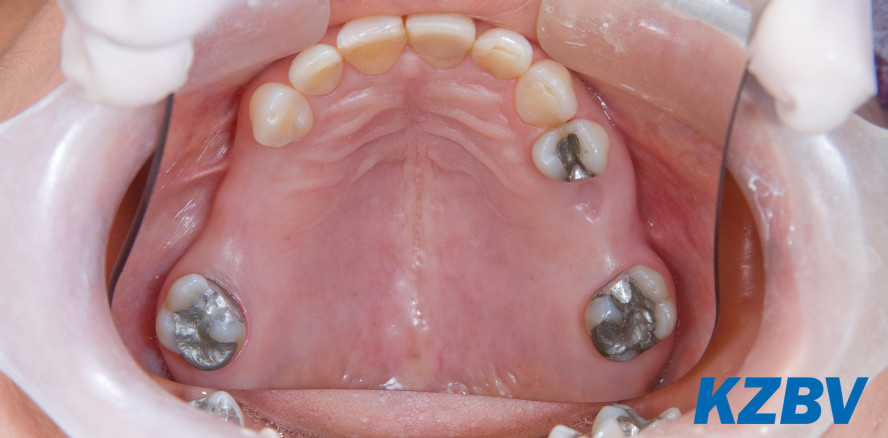

Dentalamalgam darf nach der EU-Quecksilberverordnung seit dem 1. Juli 2018 grundsätzlich nicht mehr für zahnärztliche Behandlungen von Milchzähnen, von Kindern unter 15 Jahren und von schwangeren oder stillenden Patientinnen verwendet werden. Eine Ausnahme von der Regelung besteht nur dann, wenn der Zahnarzt eine solche Behandlung wegen spezifischer medizinischer Erfordernisse als zwingend notwendig erachtet. Hintergrund der neuen Bestimmung ist das Übereinkommen von Minamata, das Gesundheit und Umwelt vor Emissionen und Freisetzungen von Quecksilber und Quecksilberverbindungen schützen soll.

Im Jahr 2016 wurden in Deutschland etwa 50,8 Millionen Füllungen innerhalb der GKV abgerechnet. Ihre Zahl ist seit Jahren rückläufig - ein Indiz für die weitere Verbesserung der Mundgesundheit und das Ergebnis der erfolgreichen Umorientierung hin zu einer präventionsorientierten Versorgung. Dentalamalgam ist in den Praxen zuletzt immer seltener verwendet worden. Das Material entspricht oftmals nicht mehr den Wünschen der Patienten. Aus ästhetischen Gründen werden häufig zahnfarbene Füllungen bevorzugt.